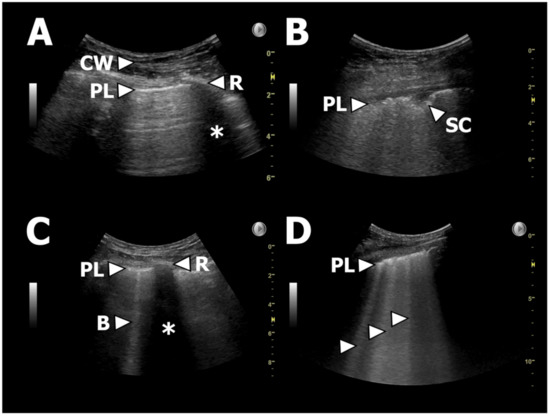

3.2. LUS Findings

4.1. LUS Findings